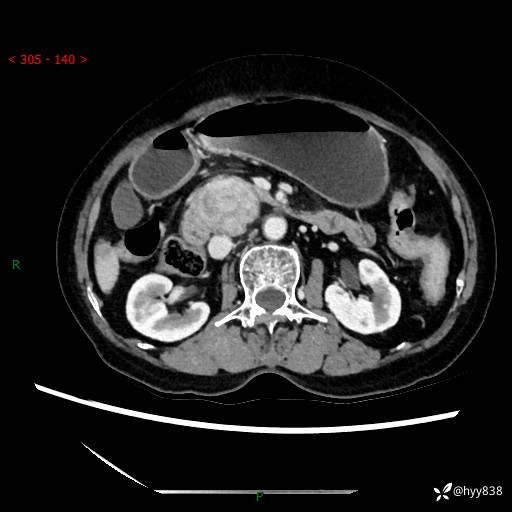

71岁/女,腹痛1月余。腹膜后肿物,间质瘤 VS 副节瘤 VS 平滑肌肉瘤---(有结果)

【患者信息】:71岁/女

【主诉】:腹痛1月余

【检查】:腹部CT增强扫描(外院CT平扫)